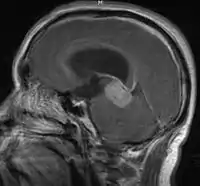

- Mainly located in midline structures, suprasellar region or pineal gland, also basal ganglia and hypothalamus

- Pineal Gland Germinoma

- Suprasellar Germinoma